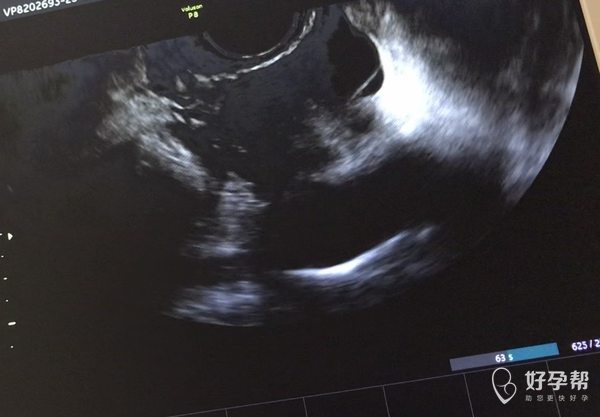

月经期查b超见图片是否提示输卵管积水还有什么

B超要图片和报告结合看,超声医生最清楚,这样留下的固定图片不能反应真实情况目前图片反应的是有盆腔积液,子宫未见异常,输卵管积液不好说,超声留的切面不好确定